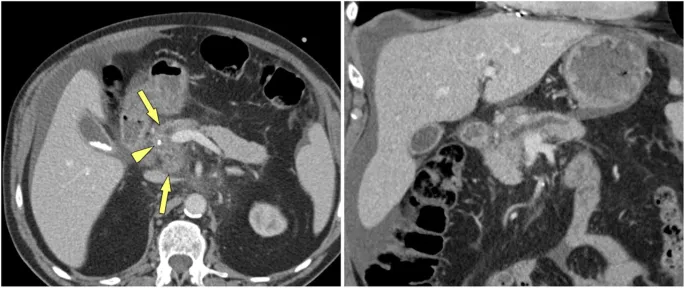

- Gross: Firm, fibrotic, often shrunken gland. Dilated ducts with calcified concretions (stones); "chain of lakes" appearance. Pseudocysts common.

- CT Scan (CECT): Initial choice; detects calcifications, ductal changes, atrophy.

- Pancreatic calcifications on imaging (CT/X-ray) are highly diagnostic.

- ERCP/MRCP often shows "chain of lakes" appearance due to ductal strictures and dilations.